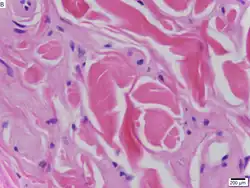

Während des Ersten Weltkriegs kam er als Arzt an der Front zum Einsatz[2] und wurde schwer verwundet.[3] Wiethe arbeitete ab 1918 als Hilfsarzt und ab 1926 als Assistent an der Wiener Hals-Nasen-Ohren-Klinik.[2] Er veröffentlichte zahlreiche medizinische Fachaufsätze.[4] Gemeinsam mit Erich Urbach beschrieb er 1929 erstmals die Erbkrankheit Urbach-Wiethe-Syndrom.[5] Wiethe spezialisierte sich auf Erkrankungen des Kehlkopfs und behandelte Sängerinnen und Sänger der Wiener Staatsoper und Mitglieder der Wiener Sängerknaben.[6] Zu seinen prominenten Patientinnen und Patienten zählten Marta Eggerth, Maria Jeritza, Jan Kiepura und Leo Slezak.[7] Er habilitierte sich 1933 an der Universität Wien. Von 1936 bis 1938 war er als Vorstand der Hals-Nasen-Ohren-Abteilung des Spitals der Wiener Kaufmannschaft tätig.[2]